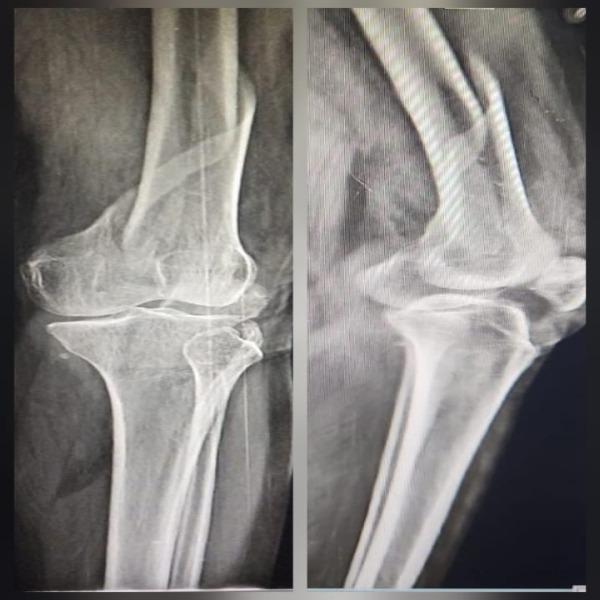

Non union of distal femur intraarticular fracture with implant failure operated elsewhere !